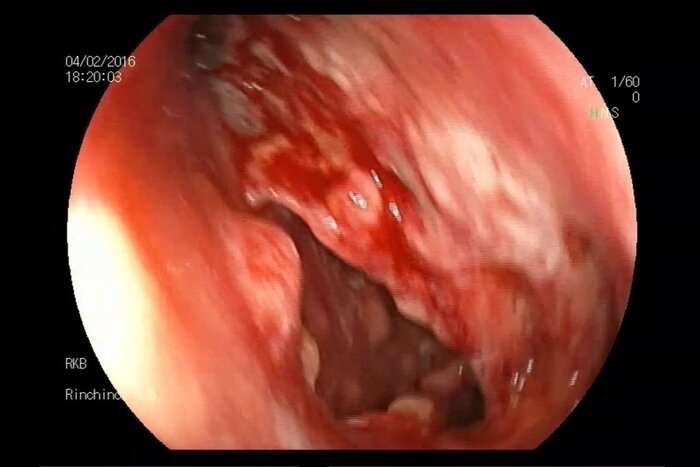

Рентген показал, что легкие не задеты, однако в мягких шейных тканях перед трахеей обнаружилось чрезмерное скопление воздуха. Компьютерная томография подтвердила: у больного обширная эмфизема в шее и грудной клетке, налицо была и перфорация глотки. Окончательный диагноз звучал зловеще: спонтанный разрыв пищевода, также известный как синдром Бурхаве. (Рентгеновский снимок шеи. Черной стрелкой показаны скопления воздуха, белой — обширная эмфизема перед трахеей.)

На шее стрелкой показана эмфизема, в грудной клетке возле позвонка T9 — эмфизема средостения Опасаясь, что у чихуна разовьется инфекция или в грудной полости зародятся воспаления, медики оставили его в лечебнице, долгие дни пичкали антибиотиками и кормили через трубку, засунутую в носоглотку и ведущую в желудок. Бр-р-р, короче. На больничном режиме страдалец пробыл несколько недель, потом еще пару месяцев за ним вели пристальное наблюдение, не случатся ли рецидивы. Но, к счастью, обошлось.